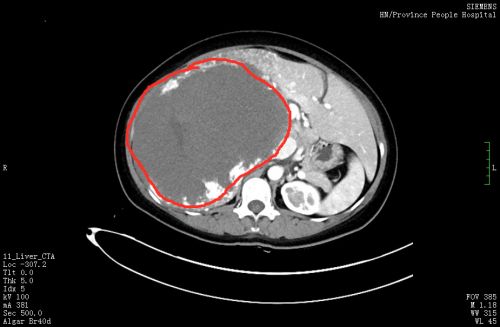

患者肝脏巨大血管瘤几乎占据整个上腹部。

切下的血管瘤约32×25×10cm3大小、重达5.5公斤。

女子半年来肚子越长越大,活像身怀六甲,没想到竟然是肝脏上面长了个巨大的血管瘤。肿瘤达到2个足月胎儿的重量,几乎占据她整个上腹部,还合并 “卡梅综合征”,手术可谓难上加难。捷克论坛 肝胆团队迎难而上,成功切除肿瘤,让女子重获新生。

6月28日,手术由陈晨副主任医师、段文斌博士团队在肝胆外科专家蒋波教授、汪新天教授和彭创教授的指导下进行。进腹后发现,一个约32×25×10cm3大小的巨大肝血管瘤几乎占据患者整个上腹部,手术切除难度极大。在手术团队的群策群力和谨慎操作下,顺利完成解剖性右半肝联合肝血管瘤切除手术,切下的肿瘤重达5.5公斤,差不多有2个足月胎儿的重量。